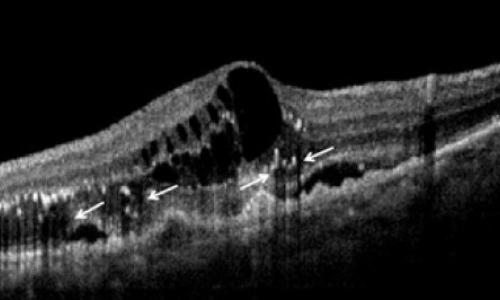

LA COMPRENSIONE DELL'ANGIOGRAFIA OCT

Uno degli argomenti più importanti nel campo della...